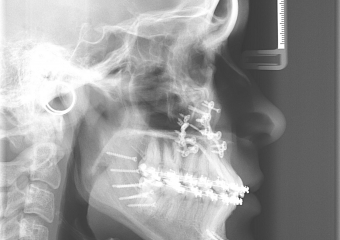

Telerradiografia após a cirurgia